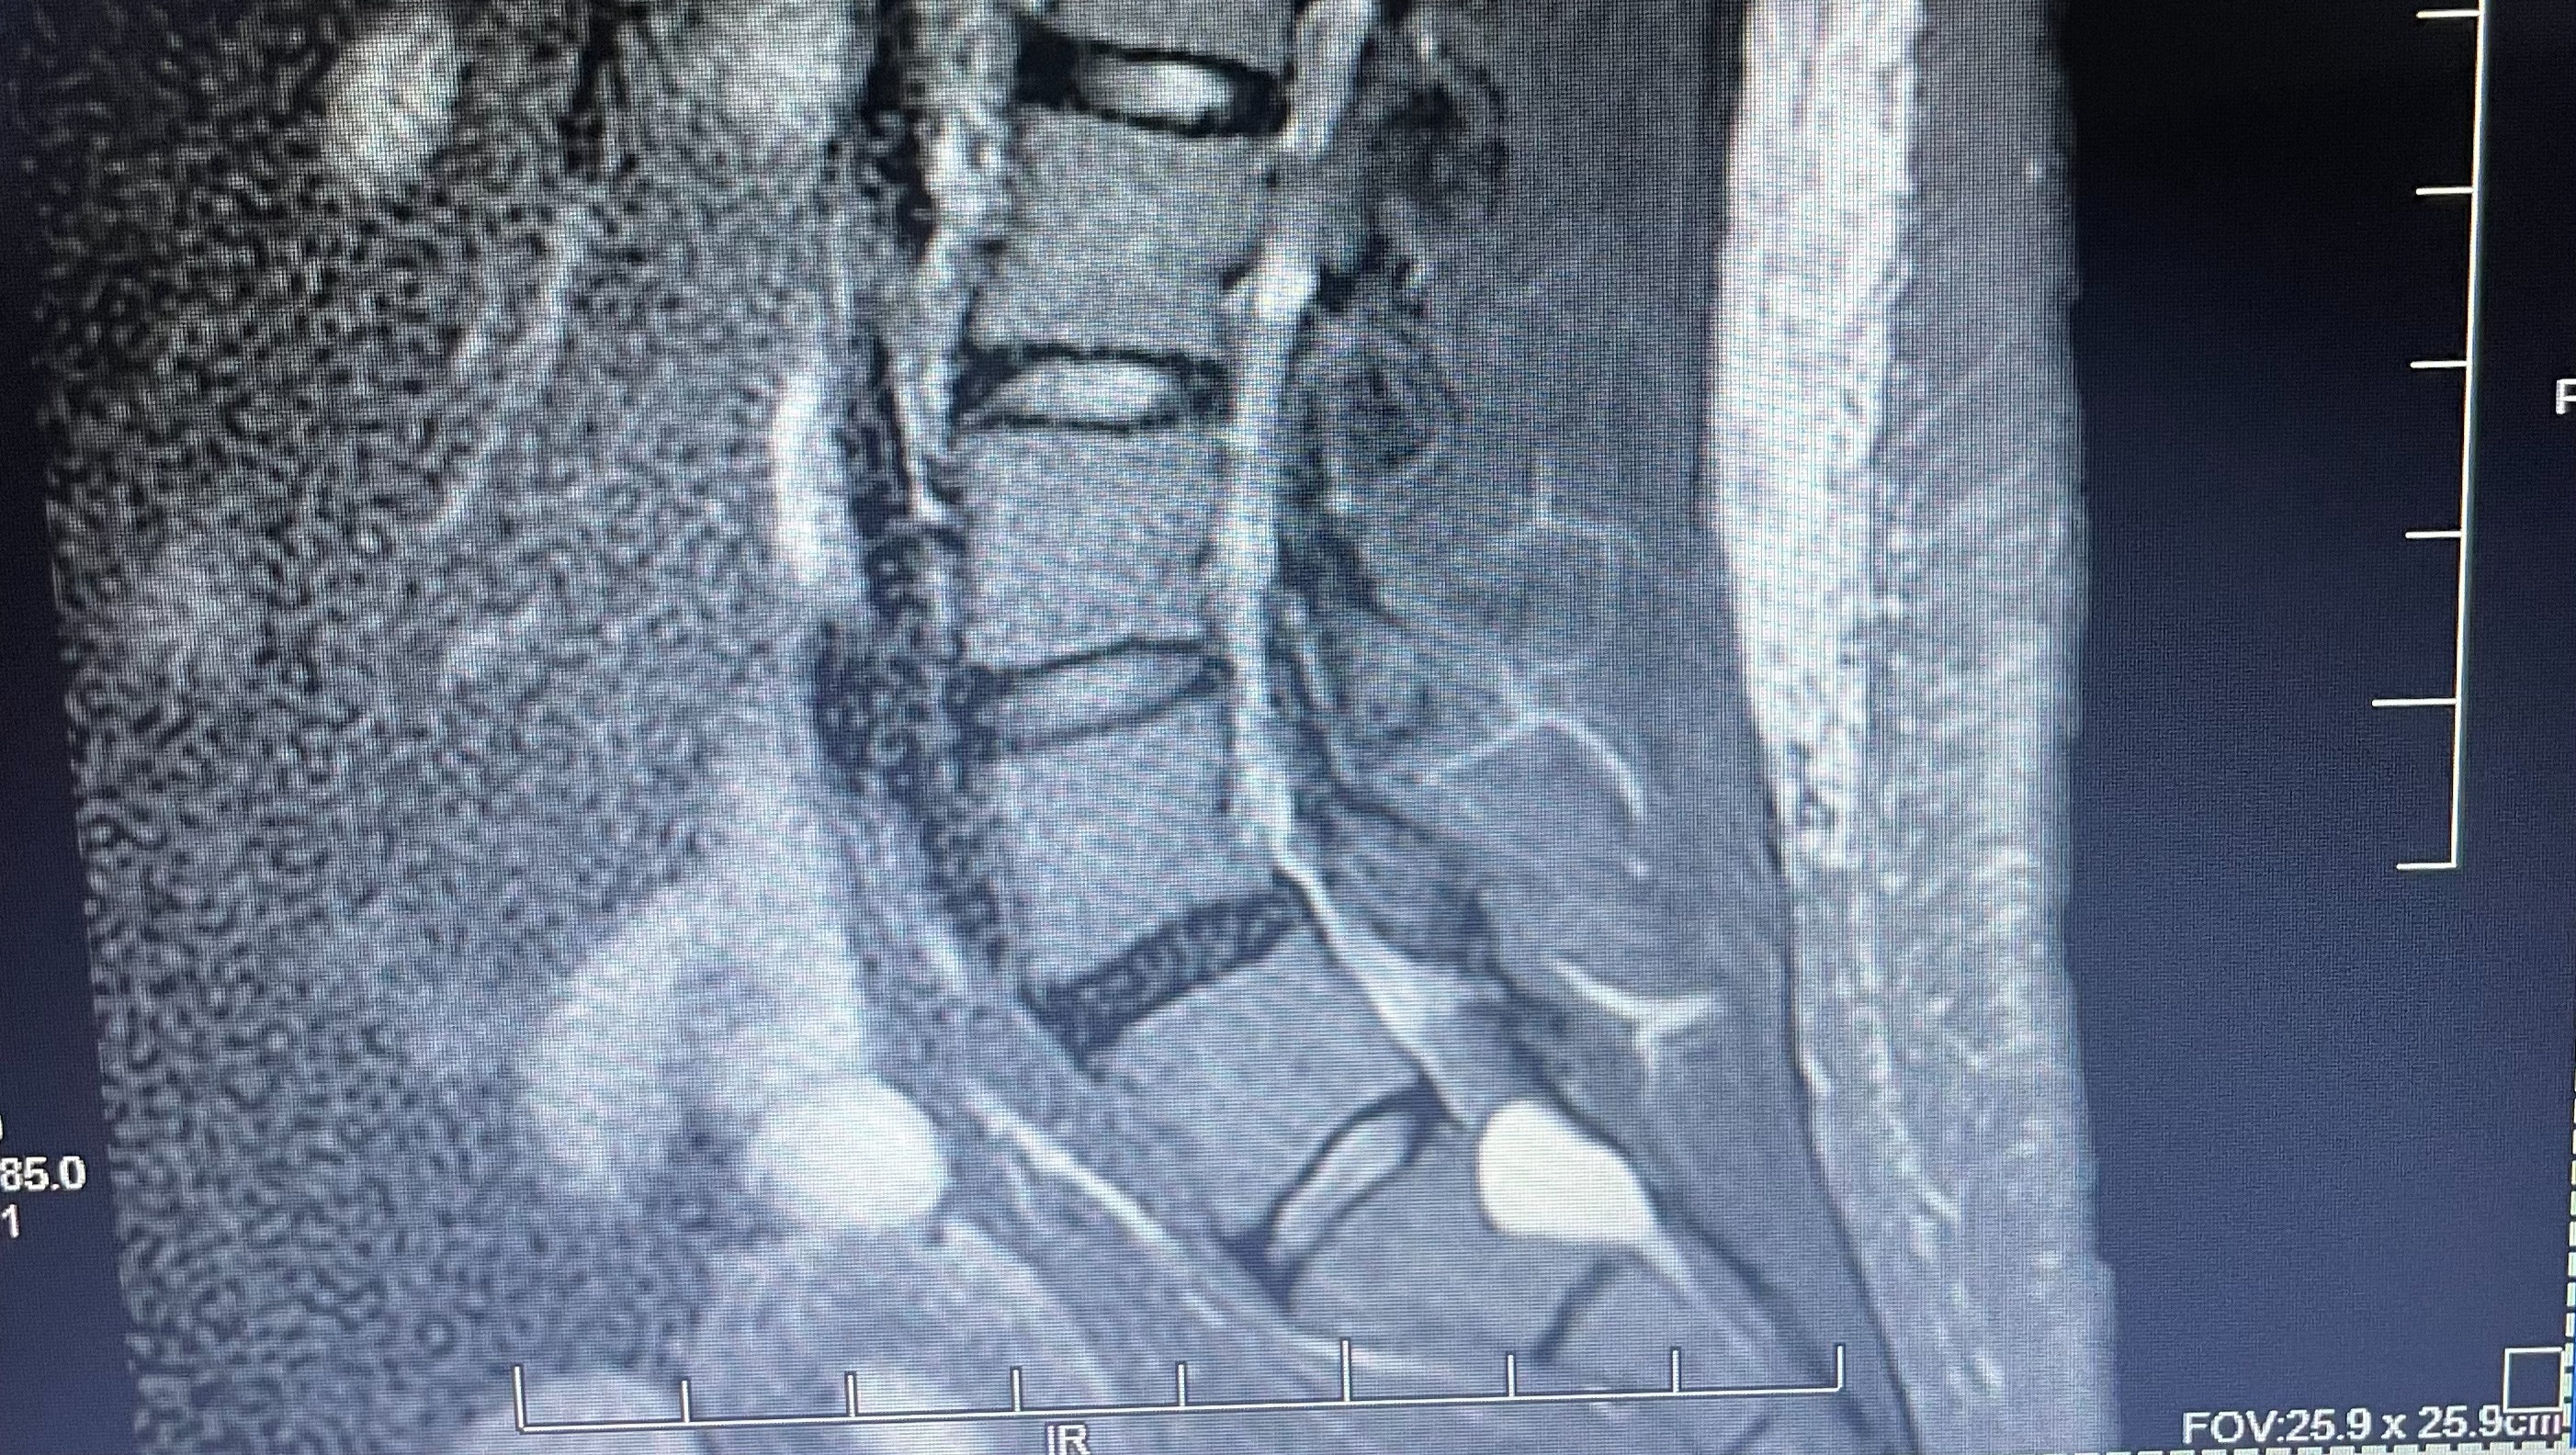

In the spring of 2023, I noticed some lower back pain that would come and go, usually after providing cares to a patient or after standing up after sitting. I was usually able to walk off the soreness and stiffness. That July, I had my first ER visit. The doctor and I both agreed that it was likely sciatica. After a couple of months, another trip to the ER and an MRI, it was determined that I have a 2-centimeter Tarlov cyst in my sacrum at the S1 level.

There are just a handful of specially trained doctors in the United States who have the skill to surgically treat TCD, which makes finding proper care extremely difficult. Of these specialists, 2 of them offer free phone consultations and they are ALL out of state. I have consulted with Dr. Frank Feigenbaum, one of the leading TCD specialists. Upon review of my scans, I'm told that I have not just one, but 3 Tarlov cysts. There is also significant erosion of my sacral bone.